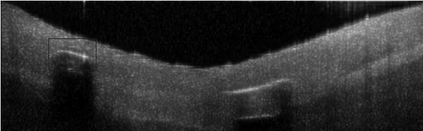

Coronary artery disease (CAD) is a cardiovascular condition with high morbidity and mortality. Intravascular optical coherence tomography (IVOCT) has been considered as an optimal imagining system for the diagnosis and treatment of CAD. Constrained by Nyquist theorem, dense sampling in IVOCT attains high resolving power to delineate cellular structures/ features. There is a trade-off between high spatial resolution and fast scanning rate for coronary imaging. In this paper, we propose a viable spectral-spatial acquisition method that down-scales the sampling process in both spectral and spatial domain while maintaining high quality in image reconstruction. The down-scaling schedule boosts data acquisition speed without any hardware modifications. Additionally, we propose a unified multi-scale reconstruction framework, namely Multiscale- Spectral-Spatial-Magnification Network (MSSMN), to resolve highly down-scaled (compressed) OCT images with flexible magnification factors. We incorporate the proposed methods into Spectral Domain OCT (SD-OCT) imaging of human coronary samples with clinical features such as stent and calcified lesions. Our experimental results demonstrate that spectral-spatial downscaled data can be better reconstructed than data that is downscaled solely in either spectral or spatial domain. Moreover, we observe better reconstruction performance using MSSMN than using existing reconstruction methods. Our acquisition method and multi-scale reconstruction framework, in combination, may allow faster SD-OCT inspection with high resolution during coronary intervention.